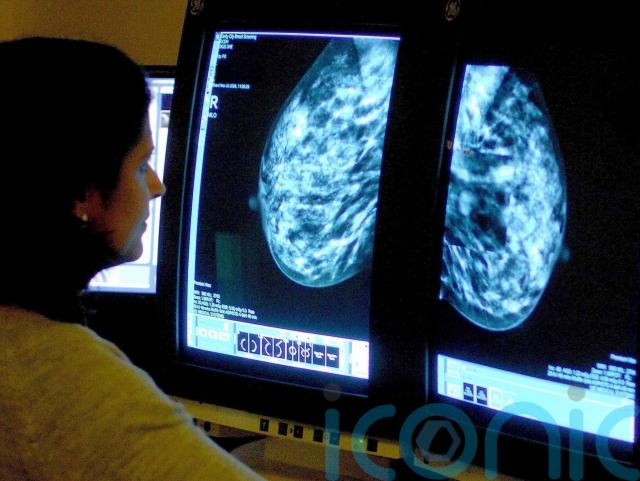

A mammogram is a breast x-ray which looks for signs of cancer, according to the charity Breast Cancer Now.

– What happens during a mammogram?

During a mammogram, a female doctor asks the patient to remove their clothes from the waist up and stand in front of the mammogram machine.

The breasts are placed one at a time on the x-ray machine and images of each breast are taken.

The scan itself should only take a few minutes, while the whole appointment should take about half an hour, according to the NHS website.

Mammograms are not often used in women under 40 as younger women have denser breast tissue, which can make the x-ray image less clear and changes harder to identify, according to Breast Cancer Now.